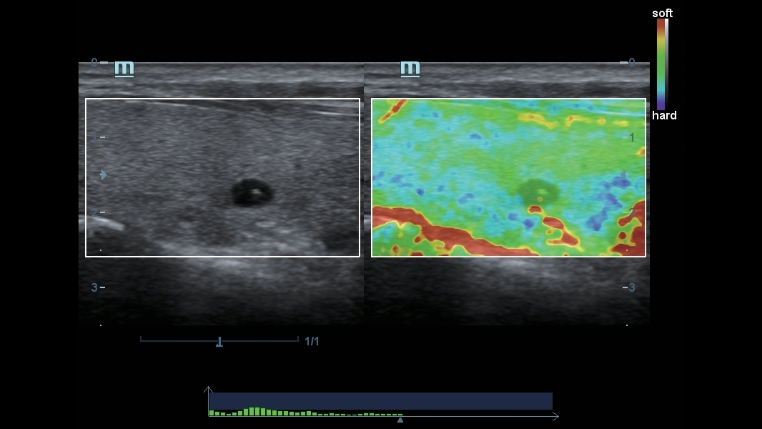

TecnologĂas de imagen clĂĄsicas: aumenta la calidad del diagnĂłstico

Mediante la aplicaciĂłn de tecnologĂas de imagen clĂĄsicas, que se migran desde los sistemas de ultrasonido establecidos, DC-40 con Full HD le proporciona una calidad de la imagen mĂĄs detallada y nĂtida.

- iClear (TecnologĂa de imagen con reducciĂłn de moteado)

- PSH (ImĂĄgenes por armĂłnicos con desplazamiento de fase)

- iBeam: tecnologĂa de formaciĂłn de imĂĄgenes espaciales compuestas

Transductores ComboWave

En comparaciĂłn con los sensores tradicionales, los transductores ComboWave utilizan un nuevo tipo de material piezoelĂ©ctrico compuesto que optimiza notablemente el espectro acĂșstico y reduce la impedancia acĂșstica. AdemĂĄs de integrarse con la tecnologĂa Ășnica 3T de Mindray, los transductores lineales ComboWave ofrecen un rendimiento sobresaliente con una gran resoluciĂłn de imagen y uniformidad en ecografĂas vasculares, de tiroides, de mama, etc.